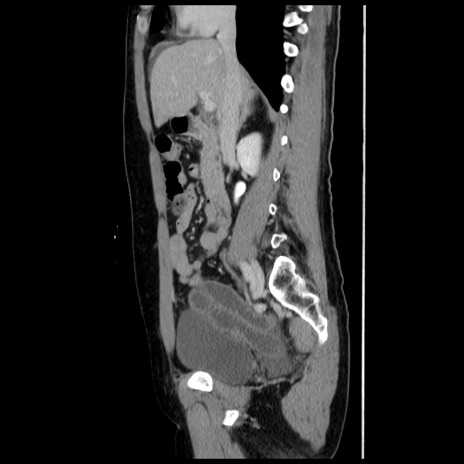

症例10(矢状断像)

【症例】 50歳代女性

【主訴】 腹痛

【現病歴】前日生レバーを食べた。今朝に排便あり。 昼前に突然発症の腹痛を生じ、当院救急外来を受診した。

【既往歴】 子宮筋腫にてで子宮全摘後

【身体所見】 意識清明、腹部:平坦、軟、下腹部やや左を中心に圧痛・反跳痛あり、筋性防御あり

【データ】WBC 7800、CRP 0.07